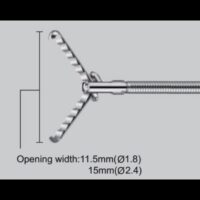

Sonde convexe (2.0-6.0MH)

Sonde linéaire (5.0-10.0MH)